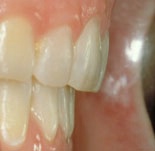

trångställt bett före behandling trångställt bett efter behandling

Före behandling av trångstätt bett Efter behandling av trångställt bett

Ett trångställt bett med för smal käke, i vy mot gommen. Således en kombination av en malocklusion och en utrymmesanomali. Om man behandlar liknande anomalier i rätt tid under ungdomsåren kan man till och med, som här, bredda käken med hjälp av tandreglering. Barnets egen växt hjälper till.